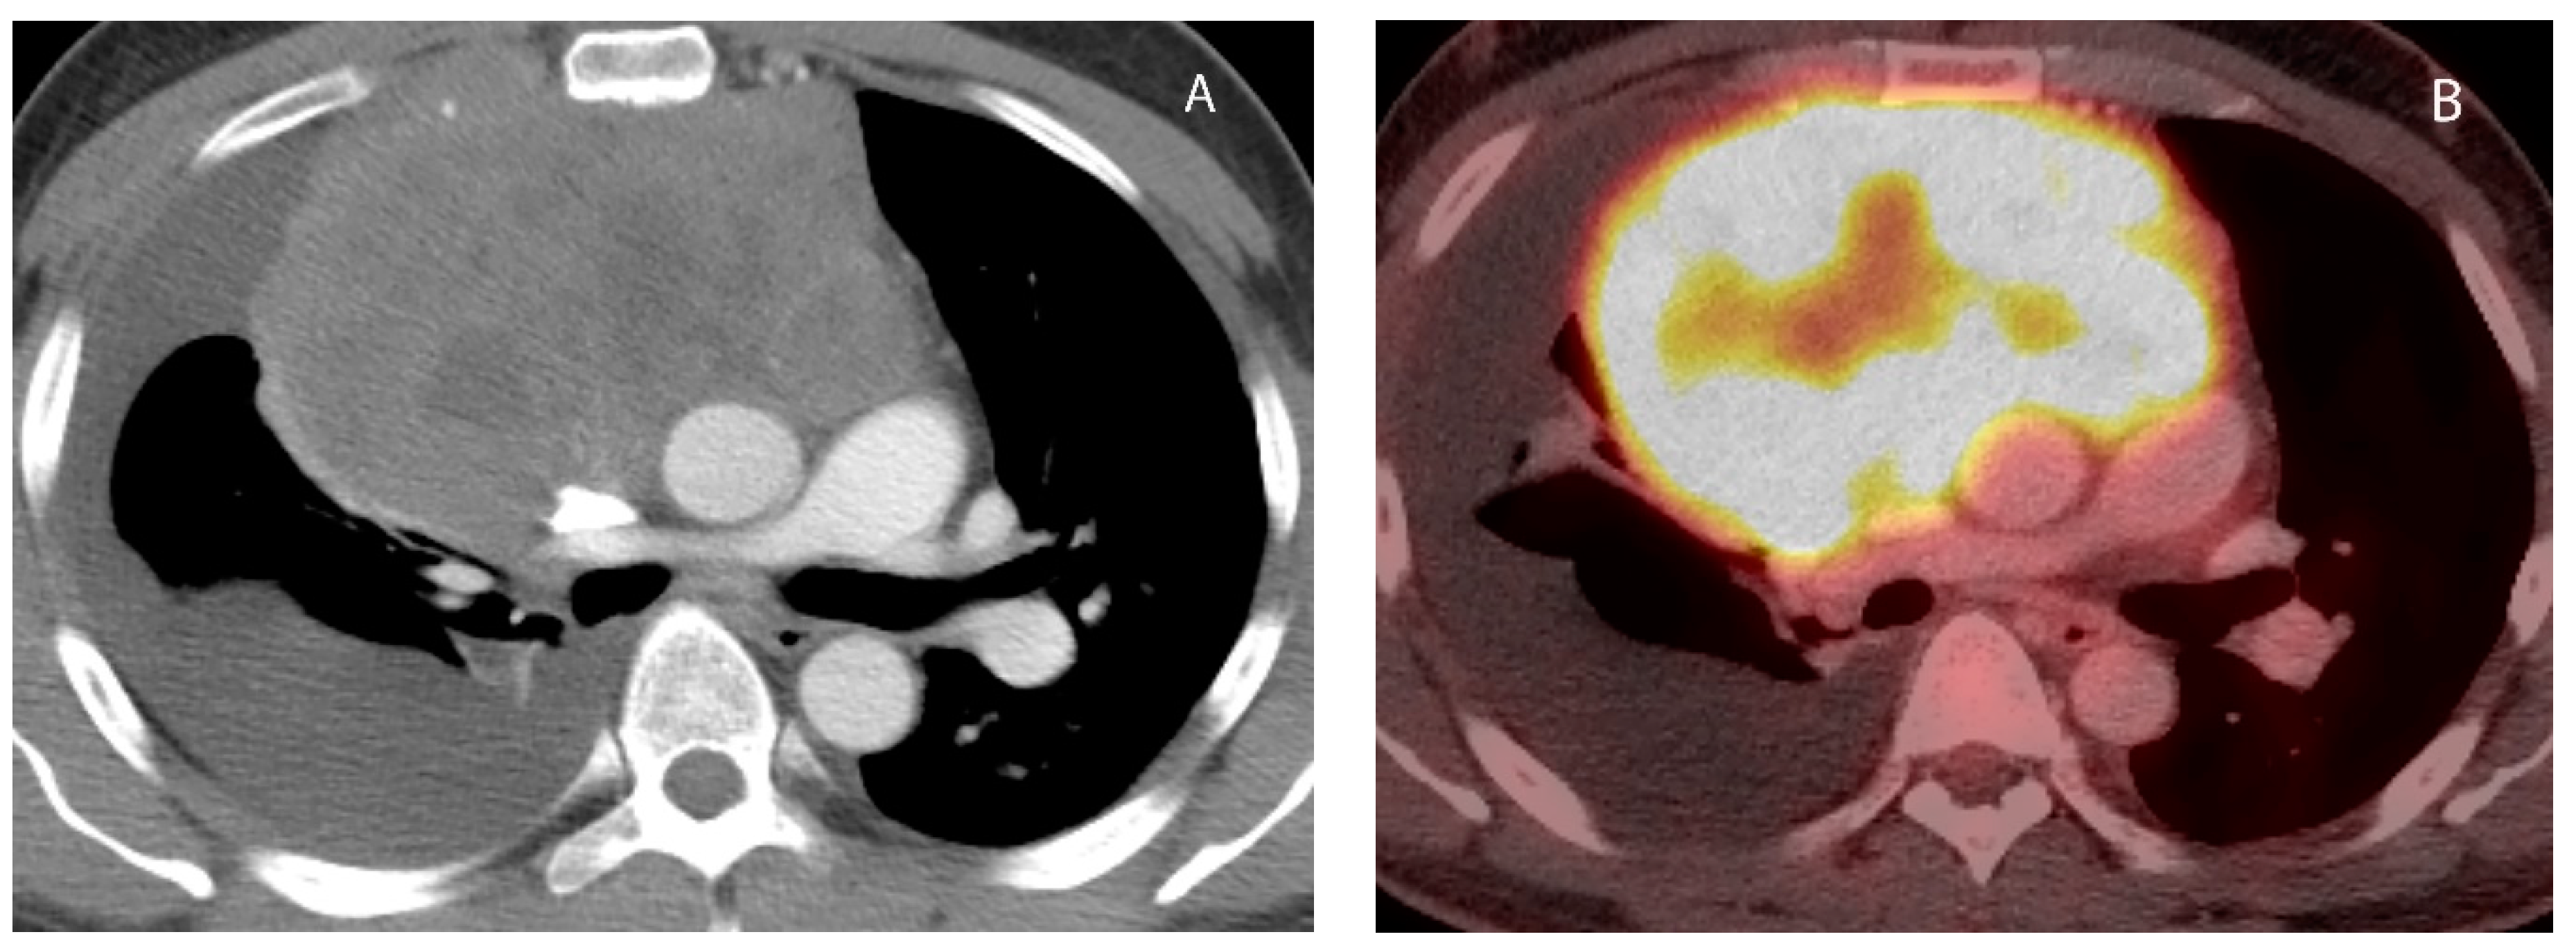

6. Lymphoma

9. Hypervascular Lesions